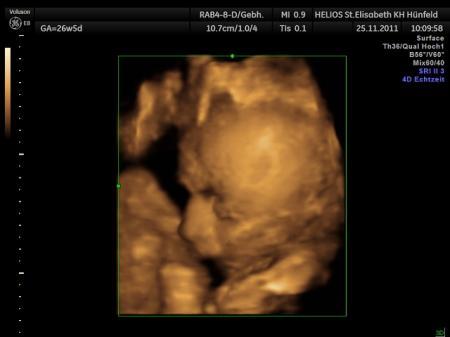

.... so hatte mein erstes CTG alles super, keine Wehen, Herzele pocht gesund und hat sich kräftig bewegt !!! Gewicht von meiner Süssen 1890 gramm, Größe 36 cm !! Alles Super, bis auf wieder 4 Kilo mehr in 4 Wochen !!! Tja weiß au woher, seit ich diese Schambeinschmerzen habe, kann ich meinen täglichen Spaziergang nicht mehr machen und mein Arzt hat mir weiteres Schonen verordnet, um die Schmerzen a bisssele in den Griff zu bekommen !!! Klar könnte jetzt meine Essmengen reduzieren von wegen, will net !!! Lg

Bild zu